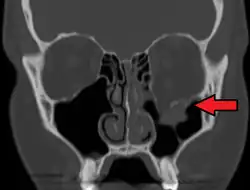

Radiography, imaging of tissues using X-rays, is used to rule out facial fractures.[2] Angiography (X-rays taken of the inside of blood vessels) can be used to locate the source of bleeding.[11] However the complex bones and tissues of the face can make it difficult to interpret plain radiographs; CT scanning is better for detecting fractures and examining soft tissues, and is often needed to determine whether surgery is necessary, but it is more expensive and difficult to obtain.[4] CT scanning is usually considered to be more definitive and better at detecting facial injuries than X-ray.[3] CT scanning is especially likely to be used in people with multiple injuries who need CT scans to assess for other injuries anyway.[12]

At the beginning of the 20th century, René Le Fort mapped typical locations for facial fractures; these are now known as Le Fort I, II, and III fractures (right).[7] Le Fort I fractures, also called Guérin or horizontal maxillary fractures,[14] involve the maxilla, separating it from the palate.[15] Le Fort II fractures, also called pyramidal fractures of the maxilla,[16] cross the nasal bones and the orbital rim.[15] Le Fort III fractures, also called craniofacial disjunction and transverse facial fractures,[17] cross the front of the maxilla and involve the lacrimal bone, the lamina papyracea, and the orbital floor, and often involve the ethmoid bone,[15] are the most serious.[18] Le Fort fractures, which account for 10–20% of facial fractures, are often associated with other serious injuries.[15] Le Fort made his classifications based on work with cadaver skulls, and the classification system has been criticized as imprecise and simplistic since most midface fractures involve a combination of Le Fort fractures.[15] Although most facial fractures do not follow the patterns described by Le Fort precisely, the system is still used to categorize injuries.[5]